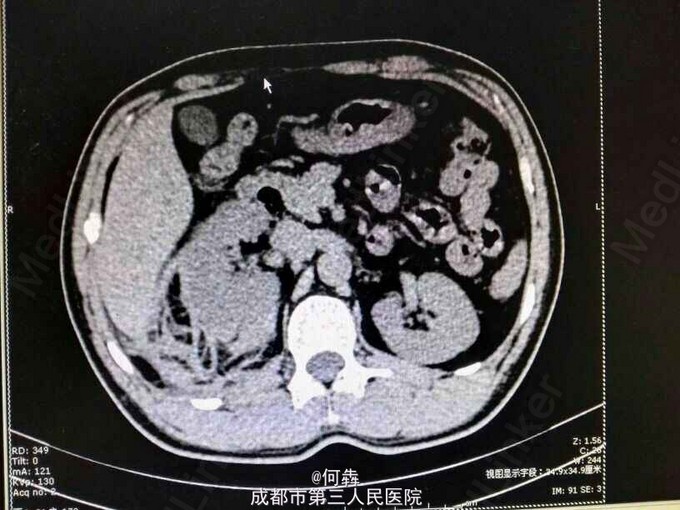

48岁男性,因“突发右腰痛1小时”入院,无血尿、外伤。既往无高血压、糖尿病。

右肾区扣痛阳性,余阴性。

右肾占位伴出血。入院后6天在全麻下行右肾部分切除术。术中冰冻及术后病检见图片